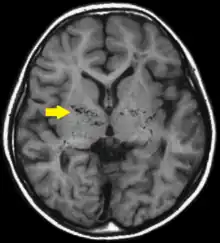

| T1-weighted MR image of moyamoya disease. Flow void in the basal ganglia is indicated by the arrow. | |